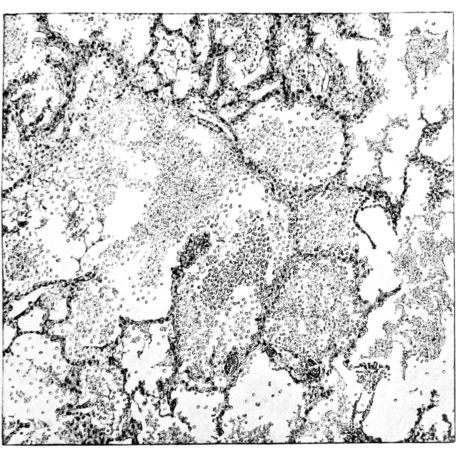

No matter what the portion of the lung from which the sections are derived, the fundamental changes found are the same. The subpleural sheets are spread wide apart, now by empty spaces, now by coagulated fluid. The process extends from the surface through the interlobular septa (Fig. XX), and is accentuated where the connective tissue is more prominent around vessels and bronchi. The nature of the infiltrate in the subpleural and interstitial tissues becomes more evident in the alveoli, which likewise are filled. The material varies somewhat in appearance, probably dependent upon its proteid content. Not infrequently the alveoli contain a homogeneous, pink-staining mass, which resembles the colloid of the thyroid gland. Again, it may be simply a coarse granular precipitate (Fig. XXIII), and in still other instances, small sticks and strands form the bulk of the alveolar content (47, 92, 140, 156). This subpleural, interstitial, perivascular, peribronchial, and alveolar edema, which is a term applicable to this collection of fluid, is very prominent, and although its intensity varies in different portions of the lung; and although it may be replaced in some areas by other types of exudate, unquestionably, this is the dominating expression of the inflammatory process in the early stage of the disease.

As might be expected from the gross appearance, the alveoli vary in size. At times slightly collapsed and at other times overdistended, their lumina are still the seat of the inflammatory exudate, although the mechanical change may allow of some variation in the appearance of their walls. As a rule, however, the alveolar wall is prominent and owes its conspicuousness to the tortuous, engorged vessels within. These vessels contain red blood cells almost exclusively, and on account of the partial, occasionally complete, loss of the lining epithelium, the alveolar wall appears as a huge, dilated arteriole (101) separating the lakes of coagulated material in the spaces (Fig. XXIII). There are areas, as indicated above, where the alveolar content may be more definitely arranged in the form of beaded or homogeneous strands of different caliber; the smallest resemble delicate threads. They tend to converge toward the alveolar wall like wheat in a sheaf, and often pass through this wall by way of the so-called pores of Cohn; as soon as the body of the neighboring alveolus is reached, they again present a fan-like expansion into innumerable, fine strands (Fig. XXII). Where the exudate is more fibrinous, the alveolar wall is less likely to be distended, its vessels are not so prominent, and their content of red blood cells is definitely decreased. Still this is not the most extreme type of alveolar exudate met with at this stage. Perhaps, the most striking, although not the most frequent, exudate has a superficial resemblance to a huge, red blood clot, and it may be difficult to make out the alveolar walls separating the masses of well preserved red blood cells that fill the alveolar spaces. These areas are indistinguishable from infarcts and may be associated with thrombotic arteritis in near-by pulmonary vessels (47) (Figs. XXIV and XXV). Among the red blood cells an occasional strand of fibrin, a desquamated alveolar epithelial cell, and rarely a polymorphonuclear leucocyte may be encountered. The alveolar wall itself varies in the definition of its outline. When its vessels are greatly distended, when its alveolar epithelium is gone, and when its content consists largely of red blood cells, it is difficult to distinguish from the exudate which it encloses. However, when it is more compressed or when its epithelial lining cells are still more or less intact, it may be seen as a blue-staining strand under the low power of the microscope, for the well preserved nuclei lend it prominence.